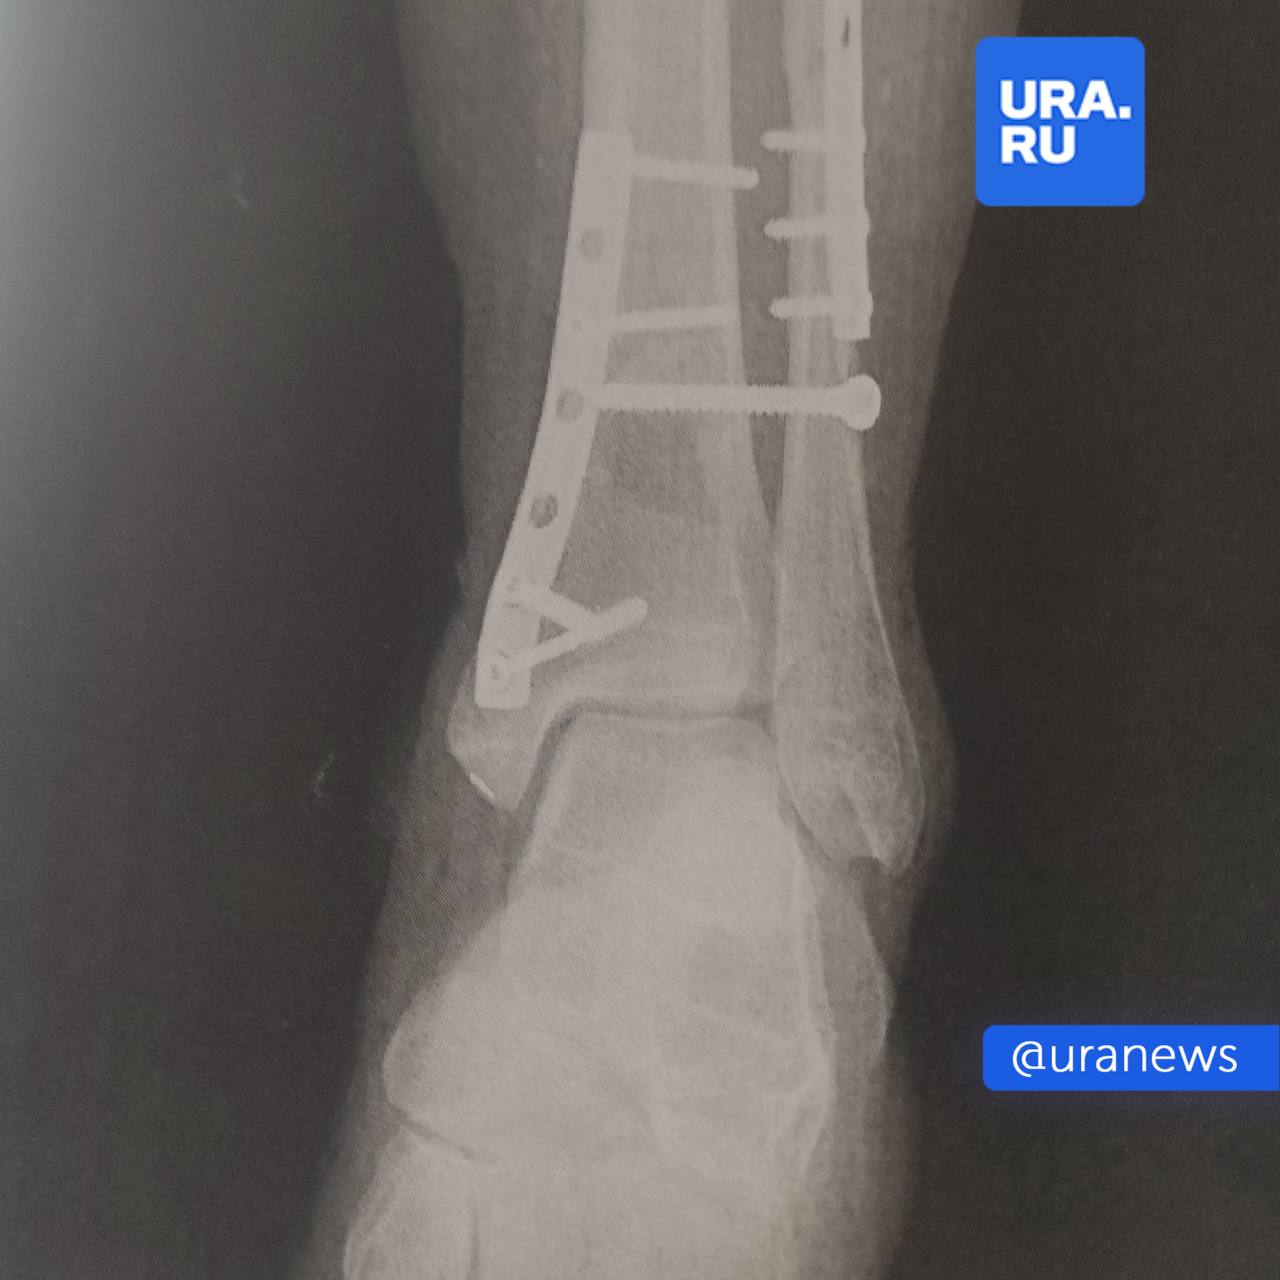

Жительнице Перми раздробило кости в фитнес-клубе — она не могла ходить два месяца и перенесла три операции.

Во время тренировки на ногу женщины рухнул 50-килограммовый груз. Она подала в суд.